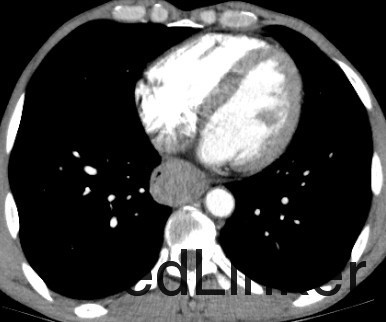

主诉:胸骨后隐痛40天,伴嗳气10天。 现病史:患者40天前无明显诱因出现胸骨后隐痛,呈间断性,无明显加重缓解因素,无放射痛。无进食哽噎感,无吞咽困难,无发热咳嗽,无胸闷心悸,无腹痛腹胀,无头晕头痛。10天前开始,患者出现嗳气不适,胸骨后疼痛无明显加重。于奈曼旗人民医院就诊,查纤维胃镜示“食管占位”。今为求进一步治疗,来我院就诊,门诊以“食管占位”为诊断收入院。患者病来一般状态好,小便正常,大便次数少,腹泻、便秘交替,饮食睡眠好,近期体重减轻约8KG。 。 既往史:否认高血压、冠心病、糖尿病等疾病史;否认肝炎结核等传染病病史;4年前颌面部外伤,否认手术史,否认输血史。否认食物及药物过敏史。预防接种史不详。

查体:T:36.4℃,P:78次/分,Bp:131/77mmHg,R:16次/分。神清语明,步入病房,查体合作,营养状态略差,皮肤粘膜无黄染,结膜无苍白,浅表淋巴结未触及肿大,气管居中,胸廓对称无畸形,呼吸运动正常,双肺叩诊清音,未及明显罗音。心音钝,律齐。腹平软,无压痛及反跳痛,肝脾肋下未触及。肝区叩痛(-),双下肢无水肿,脊柱四肢活动无异常。 辅查:胃镜(奈曼旗人民医院,2015-10-28):食管占位。

诊断 : 食管占位 治疗:入院后完善相关检查,胃镜病理未能予以确定诊断为恶性肿瘤。患者家属拒绝再次胃镜病理检查,要求行手术治疗。 后为解除梗阻症状,提升患者生活质量,按食管恶性肿瘤准备行手术治疗,术中切除肿物并剖开,内部质韧,肿物表面局部溃疡性改变,冰冻回报:平滑肌瘤伴鳞状细胞癌,患者现术后康复中,病理尚未回报。